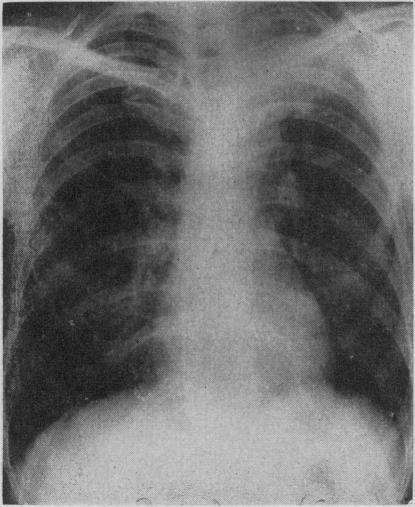

GRANDBOIS J

Can Med Assoc J. 1958 Nov 15;79(10):828-32.